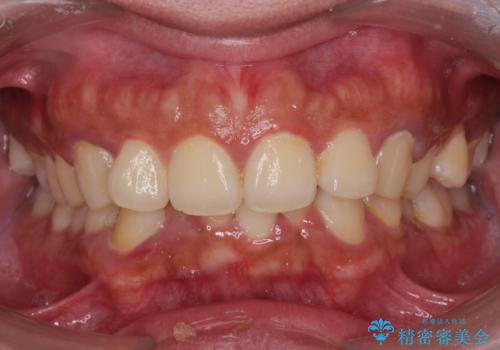

最新の症例

Latest cases